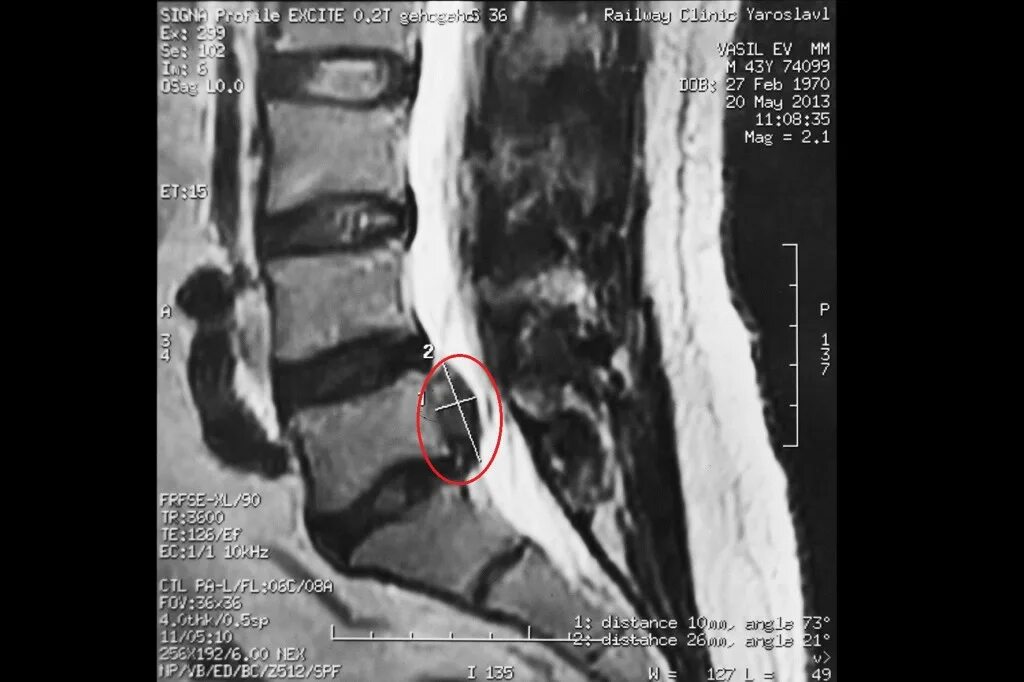

L5 s1 срединная грыжа